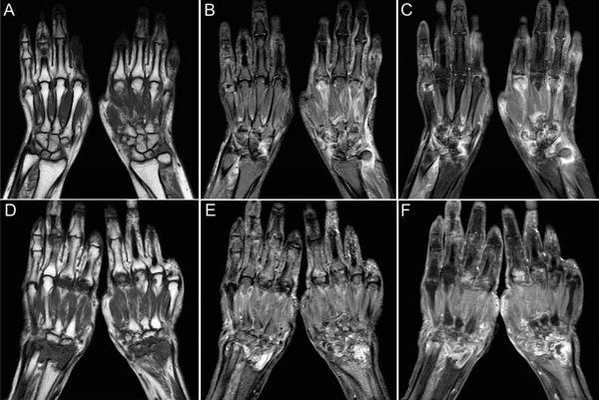

(Слева) MPT Т2ВИ в режиме подавления сигнала от жира, аксиальный срез: у пациента с признаками синдрома запястного канала (СЗК) визуализируется гиперинтенсивный срединный нерв. Усиление сигнала на Т2ВИ и компрессия срединного нерва - убедительные признаки в пользу диагноза СЗК, но они не являются ни чувствительными, ни специфичными.

(Справа) МРТ Т2ВИ в режиме подавления сигнала от жира, аксиальный срез: у пациента с тендовагинитом сгибателей и СЗК определяется умеренная выгнутость удерживателя сгибателей в ладонную сторону. Наблюдается уплощенный, но обычной интенсивности, срединный нерв. (Слева) УЗИ срединного нерва, проксимальнее входного отверстия запястного канала, поперечная плоскость: наблюдается увеличение (15 мм 2 ). Площадь поперечного сечения нерва > 12 мм 2 , что предполагает СЗК. Обратите внимание на дополнительный признак в пользу СЗК-утрата волокнистой структуры нерва.

(Справа) УЗИ входного отверстия запястного канала на уровне крючковидной кости и кости-трапеции, поперечная плоскость: визуализируется уплощенный срединный нерв с умеренным утолщением удерживателя. (Слева) УЗИ срединного нерва, продольная плоскость: наблюдается умеренная деформация по типу «песочных часов» вследствие компрессии в запястном канале. Обратите внимание на нижележащее сухожилие сгибателей.

(Справа) МРТ Т2ВИ в режиме подавления сигнала от жира, аксиальный срез, пациент со снижением чувствительности латеральной стороны кисти и слабостью в большом пальце: определяется компрессия и гиперинтенсивность срединного нерва. Наблюдается отеки и умеренная атрофия короткой мышцы, отводящей большой палец.